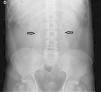

Varón de 49 años, hepatectomizado por quiste hidatídico hace 3 años. Acude a urgencias por dolor intenso en la fosa renal derecha de corta evolución, se realiza analítica: normal; ecografía abdominal: sin hallazgos, y radiografía abdominal (fig. 1): valorada como normal al inicio; tras una revisión describen la ausencia del patrón intestinal, casi en su totalidad, con burbujas aéreas en hipocondrio y fosa ilíaca derechas. Tras estabilización ingresa en planta como cólico nefrítico. A las 24h presenta deterioro clínico, realizándose TC (fig. 2): gran hernia diafragmática (1) con perforación y necrosis del intestino grueso (2) y delgado (3), desplazamiento de todas las vísceras torácicas (4 y 5). En situación de shock séptico refractario se interviene en 3 ocasiones con amplia resección intestinal por isquemia masiva. Mejoría progresiva, actualmente en domicilio, aunque con grave síndrome de intestino corto.